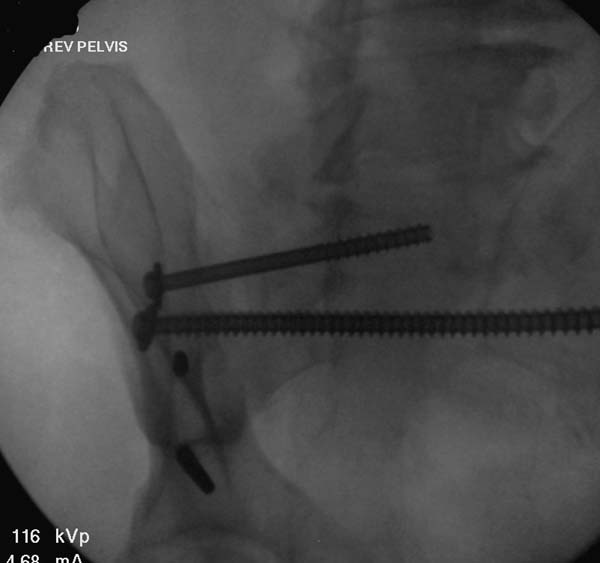

Большое спасибо всем Вам за помощь! Вчера прооперировали пациентку. Выполнили закрытую репозицию левой половины таза на тракционном столе под контролем ЭОП, закрытая фиксация левого КПС двумя каннулированными винтами. Учитывая удовлетворительное стояние отломков лонной и седалищной костей справа, а так же удовлетворительную ширину лона передние отделы стабилизировали системой ЦИТО

Послеоперационные КТ прилагаются

Винты введены в S1

Вроде бы все удалось. хорошо, что фрагмент (как выяснилось из КТ оказался небольшим), но для оценки лучше выкладывать рентген в стандартных проекциях